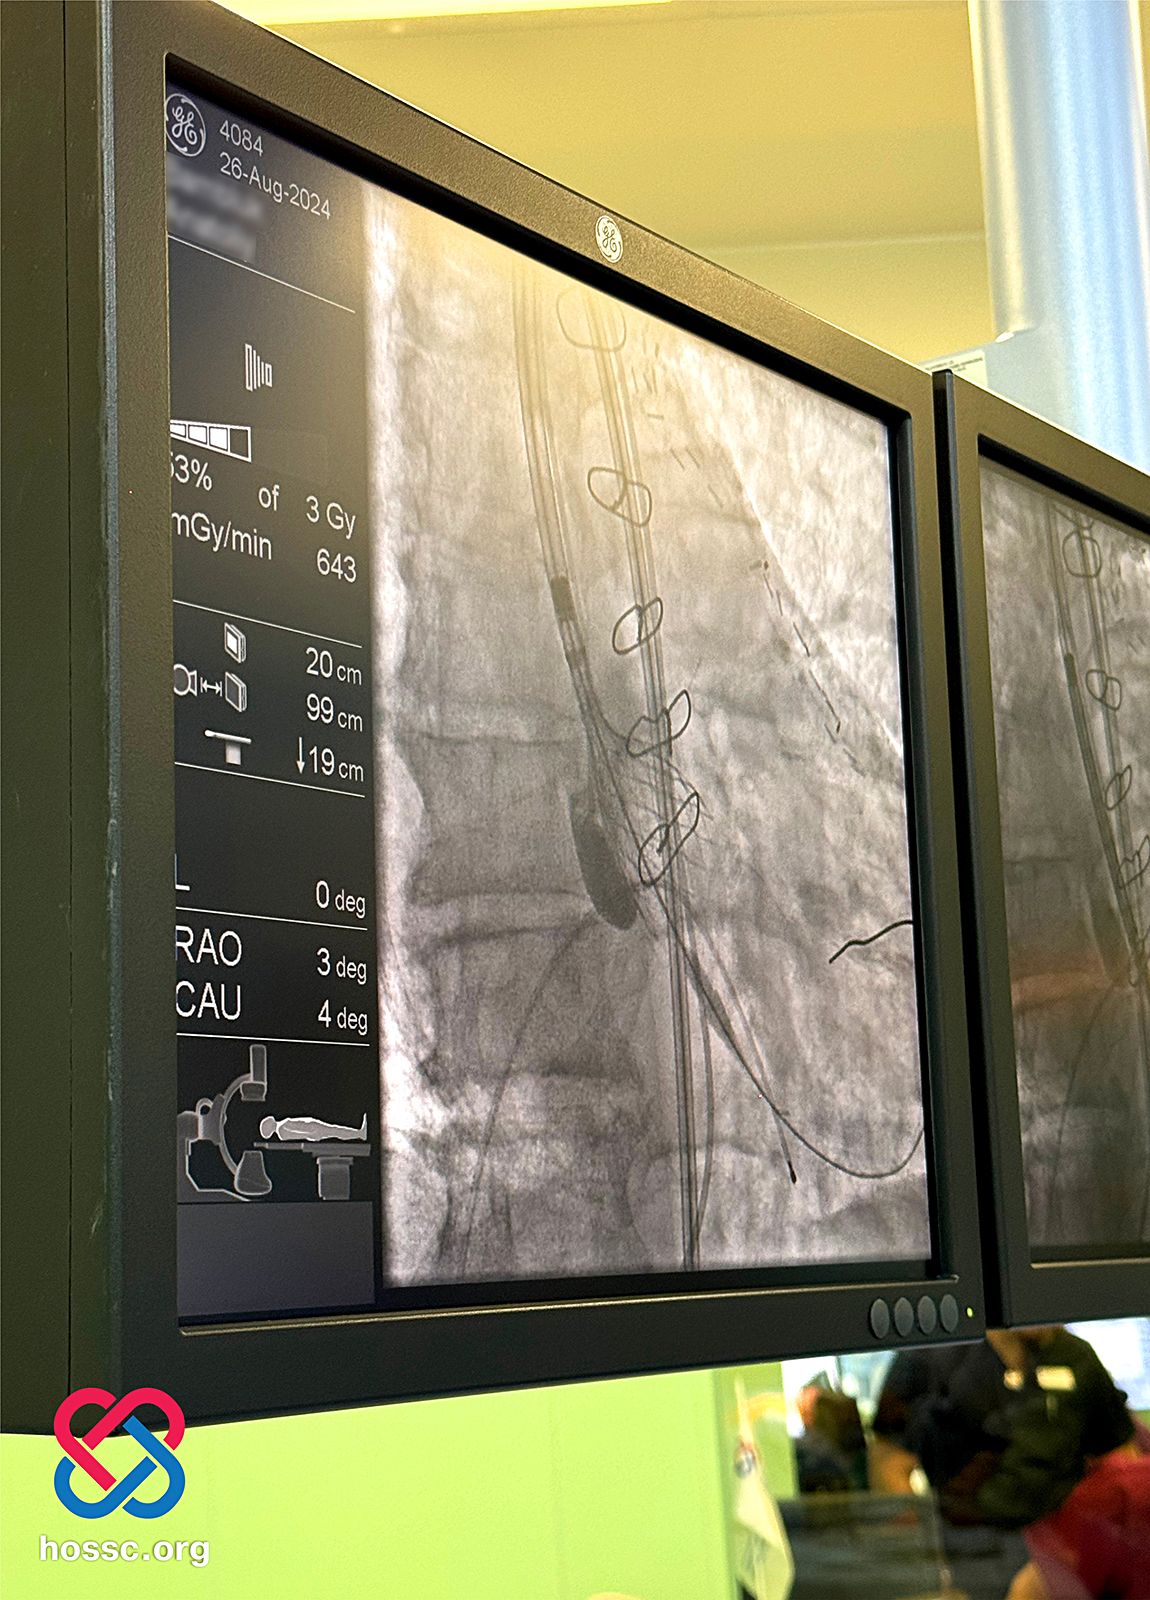

26-27 серпня, незважаючи на масовану ракетну атаку ворога, фахівці Хмельницького обласного серцево-судинного центру, спільно з колегами, провели заплановані транскатетерні імплантації аортального клапана (TAVI) трьом пацієнтам. Серед них – двоє з Київщини та один із Дніпропетровщини, який є членом родини військовослужбовця ЗСУ.

Поки сили ППО збивали російські дрони та ракети, а господарська служба центру прибирала уламки збитої техніки, команда інтервенційних кардіологів та кардіохірургів проводила високотехнологічні операції. Ці втручання здійснювались ендоваскулярно, без розрізу грудини та зупинки серця, що значно знижує ризик для пацієнтів.

Усі троє пацієнтів були літнього віку та мали критичний аортальний стеноз, який супроводжувався серйозними супутніми захворюваннями. Заміна аортального клапана через транскатетерну імплантацію (TAVI) стала для них єдиним варіантом лікування, оскільки операція на відкритому серці в умовах штучного кровообігу була б занадто ризикованою.